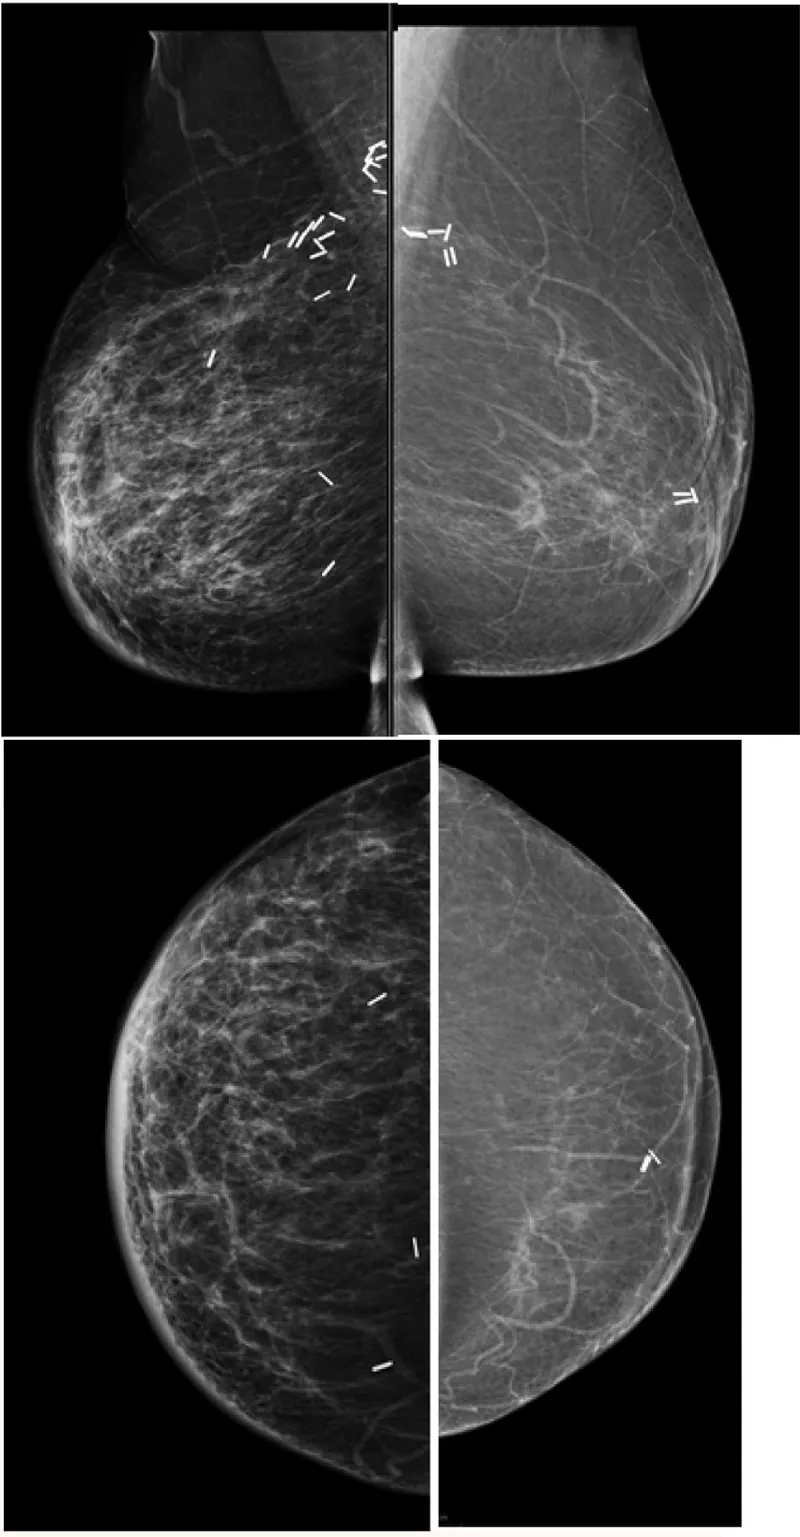

Recurrence Radar - Red Flag Recon

Key: Differentiate recurrence from benign changes.

General Red Flags:

- New/growing mass/density.

- New/increasing suspicious microcalcifications.

- Architectural distortion developing >2 years post-op.

Modality Specific Signs:

- Mammography:

- New/enlarging opacity at/near surgical site.

- New pleomorphic/linear microcalcifications.

Differentiating Benign Changes:

- Scar: Stable/retracts over time. Initial distortion possible.

⭐ Architectural distortion at the lumpectomy site developing >2 years post-treatment is highly suspicious for recurrence.

- Baseline mammogram post-treatment (lumpectomy/radiation) is crucial at 6-12 months.

- Differentiating scar (stable/shrinks) from recurrence (grows, new calcifications) is key.